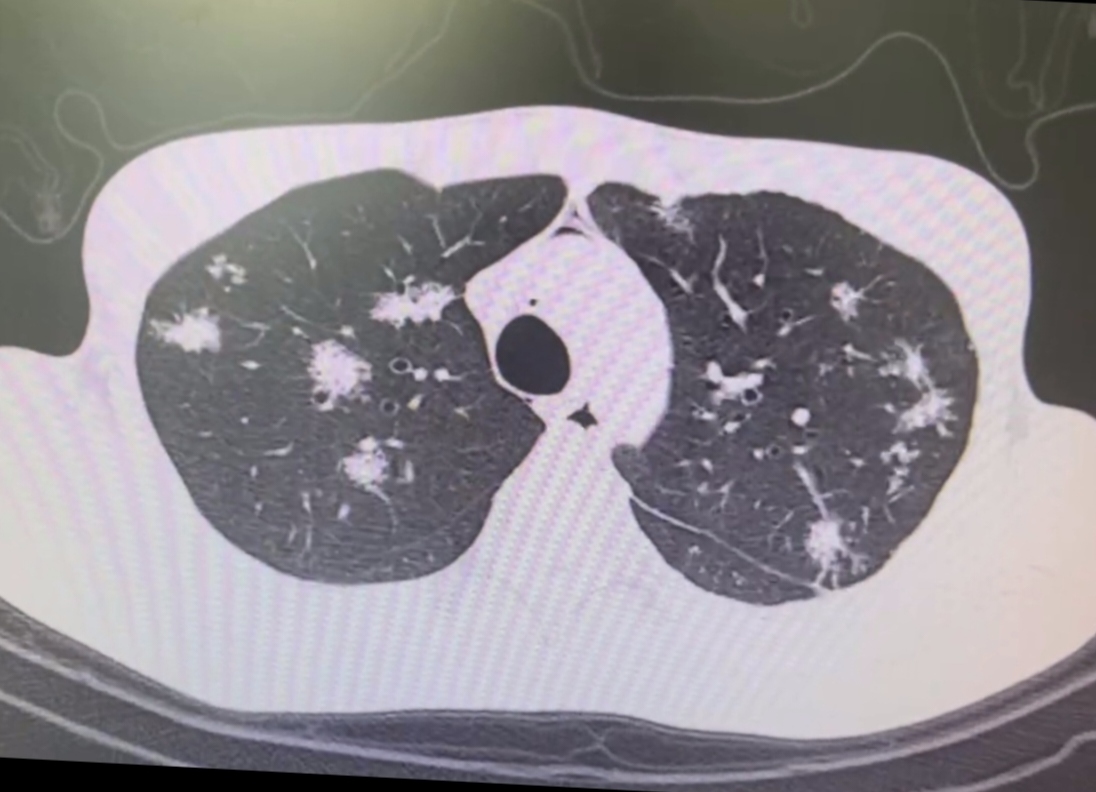

再看看這些“妖怪”的密度,就如同它們各自的“法寶”。實(shí)性結(jié)節(jié)在CT圖像上就像閃閃發(fā)光的“金疙瘩”,白白的小點(diǎn)點(diǎn)或者小塊塊,非常密實(shí)。這可能是腫瘤、感染等“妖法”造成的。

部分實(shí)性結(jié)節(jié)則像是半透明的“陰陽寶鏡”,在CT圖像上呈現(xiàn)出白色和灰色混合的區(qū)域,讓人摸不著頭腦,是好是壞,還得請(qǐng)“太上老君”多做些檢查才能確定。

磨玻璃結(jié)節(jié)就像是一片模糊的“云霧罩”,在CT圖像上看起來是一片模糊的白色區(qū)域,但還能看到下面的肺結(jié)構(gòu)。它可能是感染、炎癥這些“小法術(shù)”變出來的,也有可能是肺癌早期這個(gè)“大妖”在搞鬼。